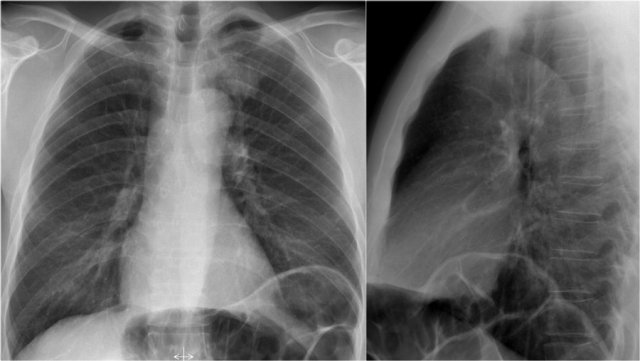

Right Ventricular Enlargement

First study the PA and lateral chest film and then continue reading.

Findings

• Chest radiographs show massive cardiomegaly, predominantly due to right ventricular dilation (yellow arrow on lateral view).

• Small aortic knob (blue arrow), with dilation of the pulmonary trunk and right lower pulmonary artery.

• Findings suggest a left-to-right shunt with secondary pulmonary hypertension.